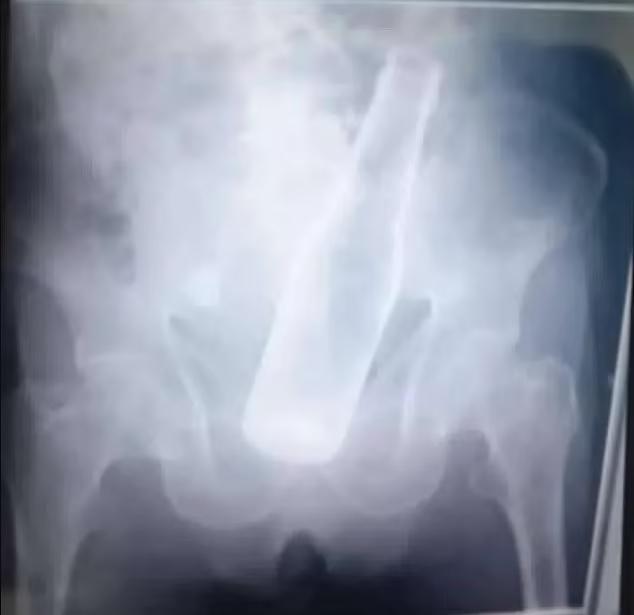

X光顯示,啤酒樽卡在老翁下腹。(互聯網)

委內瑞拉發生一宗離奇劫案,英國《每日郵報》報道,中部帕洛內格羅(Palo Negro)一名79歲老翁因體內劇痛,到醫院急症室求診,X光檢查後發現一個完整的啤酒樽卡在小腹處。老翁其後被轉送到另一間醫院,接受手術將啤酒樽取出。

老翁被送進醫院接受緊急手術,將啤酒樽取出。(互聯網)